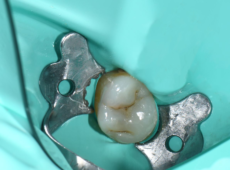

Intervento

Conservativa

Branca dell’odontoiatria che si occupa di prevenzione, diagnosi e trattamento delle carie e di altre lesioni dei denti, con l’obiettivo di preservare quanto più possibile la struttura dentale naturale.